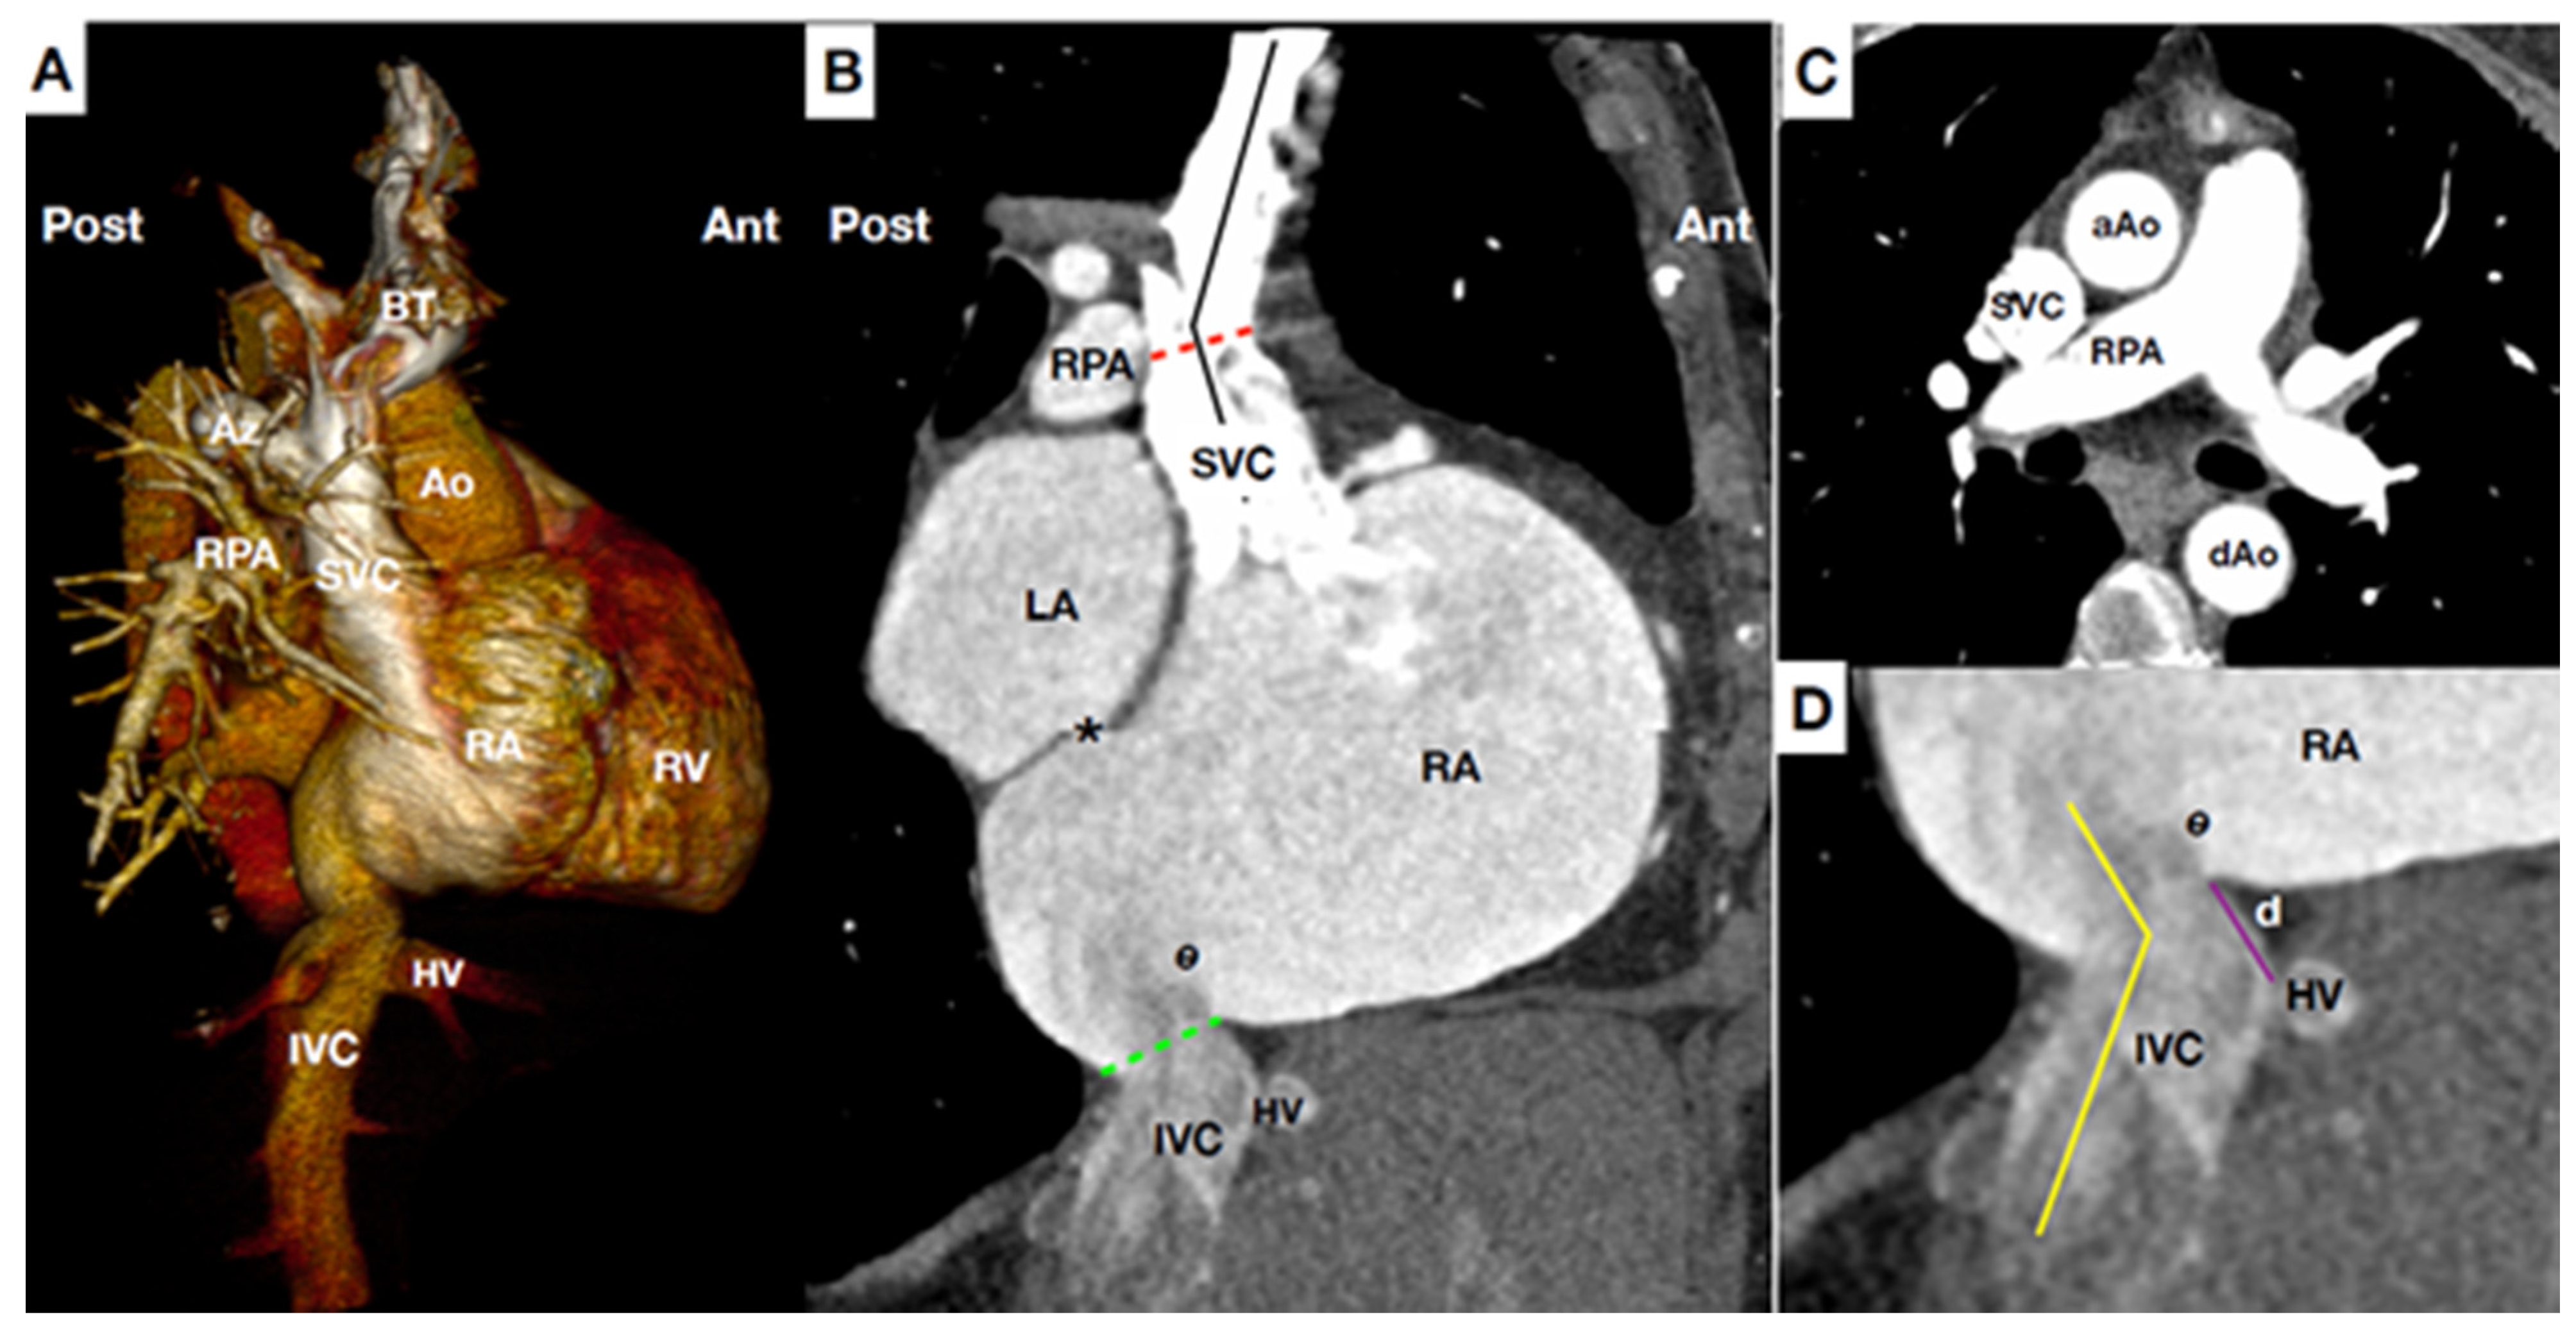

Figure 1.

Main anatomical landmarks for CAVI. (A) Computed tomography (CT) scan reconstruction of central venous system, right heart and pulmonary artery at lateral plane. (B) CT para-sagittal plane at the level of the vena cava. Superior vena cava (SVC) is usually 7.1 cm long, and has slight angulation (black line), usually at the level of right pulmonary artery (RPA) (Red line). Of note, the junction of SVC-right atrium (RA) and junction IVC-RA are not in the same anterior-posterior plane. Special caution applies to patients with short distance between the IVC-RA junction (green line) and inter-atrial-septum (*) owing to the risk of septal perforation during inferior caval prosthesis delivery. Eustachian valve (e) varies in size, may be very prominent. (C) CT transversal plain at the level of RPA. Notable structures (i.e., aorta, trachea, pulmonary artery, etc) are adjacent but not attached to SVC minimizing risk of complications during CAVI. (D) CT at para-sagittal plane of the IVC-RA junction showing the distance between hepatic vein (HV) confluence and IVC-RA junction (purple line). Higher distance at this level helps to stabilize the devices owing that it increases the contact surface between device-vein wall. The IVC-RA junction (yellow line) usually presents with a greater angulation than SVC-RA junction. Ao: Aorta. AZ: Azygos vein. BT: Brachiocephalic trunks (Innominate). dAo: descending Aorta. d.: distance between hepatic vein confluence and inferior vena cava-right atrium junction. HV: Hepatic veins. IVC: Inferior vena cava. LA: Left atrium. RA: Right atrium. RPA: Right pulmonary artery. RV: Right ventricle. SVC: Superior vena cava.